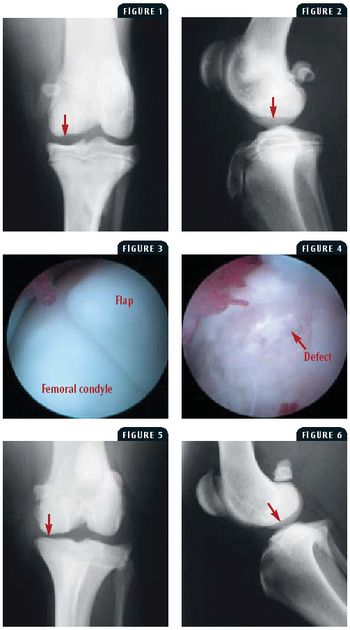

A 7-month-old intact male Labrador retriever was presented for evaluation of a two-week history of left hindlimb lameness.